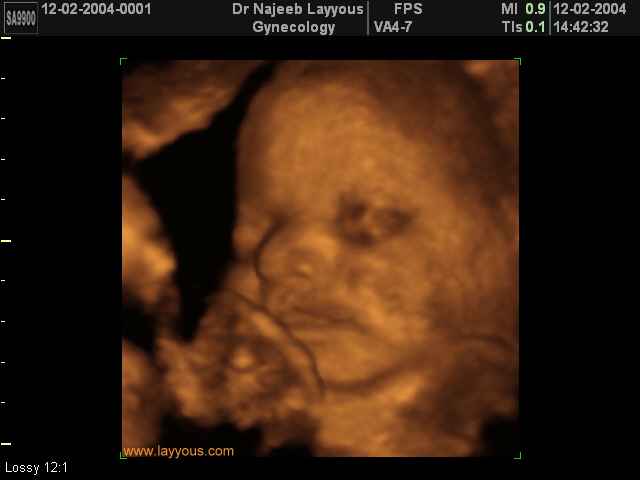

صور لوجه الجنين بجهاز الالتراساوند ثلاثي الأبعاد | الدكتور نجيب ليوس

صور لوجه الجنين بجهاز الموجات فوق صوتية ثلاثي الأبعاد